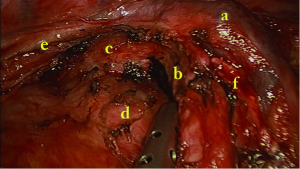

A 64-year-old female presented with a 2.0 cm × 2.0 cm × 1.0 cm nodule in posterior segment of right upper lobe and a ground glass opacity (GGO) in the left upper lobe on computed tomographic (CT) (Figures 1,2) was admitted in our institute on March 16th, 2014. The patient underwent preoperative staging and cardiac and pulmonary function assessment. PET-scan indicates no signs of metastasis. Under general anesthesia with double lumen tube, the patient underwent uniportal cVATS lobectomy for right upper lung tumor on March 19th, 2014 (Figure 3). The final pathologic TNM staging is T1aN0M0 (IA). Regular follow up was initiated for the GGO in the left upper lobe.

We begin the procedure with an exploration of the pleural cavity. The tumor is identified in the posterior segment of the right upper lobe. The frozen section analysis after wedge resection revealed infiltrating adenocarcinoma, so we proceed to right upper lobectomy with systematic lymphadenectomy.

Division and transection of truncus anterior artery

First cut open mediastinal pleura in the anterior hilum and underneath the arch of the azygos vein. Then dissect and indentify the gap between the superior pulmonary vein and truncus anterior artery. The lymph nodes are cleared at the same time. Dividing the truncus anterior artery first is often recommended in order to facilitate the insertion of the staplers for the upper lobe vein. We strongly recommend the use of silk ligation and hemolock in cases where the angle for stapler insertion is not optimal especially for the left upper lobectomy. The posterior ascending artery can be divided separately or at last together with the fissure.

Division and transection of superior pulmonary vein

The location of endostapler and the thoracoscope are interchangeable between two incisions in biportal approach. In uniportal approach, first dividing the artery is most commonly used. In unusual cases, dividing the superior vein following the truncus anterior artery and then the upper bronchus is used. Sometimes divide the minor fissure help first staple the superior vein from anterior and superior to the posterior and inferior direction.

Division and transection of right upper lobe bronchus

Identifying and clearing the lymph nodes between the upper and intermediate bronchus first. The bronchus can be transected via anterior or posterior approach by a stapler while the former is more convenient because of no need to expose the lung anteriorly.

Dissection of the horizontal fissure and the posterior halves of the oblique